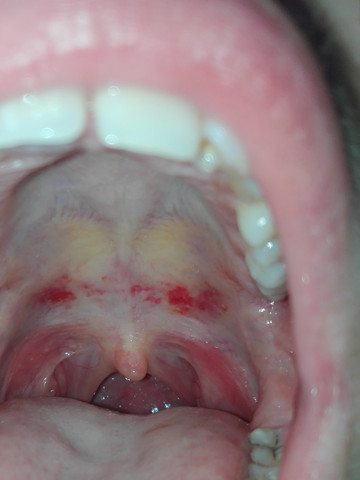

Diese wird genau untersucht. Eine Entzündung am Gaumen fällt meist durch eine schmerzhafte Schwelllung und Rötung auf. Beschwerden am gaumen bei zahnschmerzen hintergrund können zahnschmerzen sein die sich auf den gesamten mund rachen bereich ausdehnen und damit auch den gaumen betreffen können einleitung eine entzündung am gaumen fällt meist durch eine schmerzhafte schwelllung und rötung auf.

Vorgestern Abend habe ich mich beim essen in Asien verbrannt seit dem hatte ich wenn ich mit der Zunge den Gaumen berühre ein brennendes Gefühl.

Recurrent aphthous stomatitis oral apthous ulcers sind kleine weiße oder rote offene Stellen oder Geschwüre der Mundschleimhaut der Zunge oder des Gaumens. Die sorgt dafür dass aus dem Zucker im Honig Wasserstoffperoxid. Entzündung am Gaumen - Dr-Gumpert. Diese kann aufgrund von Verletzungen Infektionen allergischen Reaktionen oder gar Verbrennungen auftreten. Eine Entzündung am Gaumen fällt meist durch eine schmerzhafte Schwelllung und Rötung auf. Beschwerden am Gaumen bei Zahnschmerzen Hintergrund können Zahnschmerzen sein die sich auf den gesamten Mund-Rachen-Bereich ausdehnen und damit auch den Gaumen betreffen können Einleitung Eine Entzündung am Gaumen fällt meist durch eine schmerzhafte Schwelllung und Rötung aufDiese kann aufgrund von Verletzungen Infektionen allergischen. Ich hoffe ich bin im richtigen Forum. Der Begriff kommt aus dem Griechischen und bedeutet Schwämmchen. Beim Kauen oder bei Kontakt mit Fruchtsäure.

Hallo ich habe seit ca. Offene stelle am gaumen was tun Gaumenschmerzen. Eine Entzündung am Gaumen fällt meist durch eine schmerzhafte Schwelllung und Rötung auf. Zu diesem Zweck eignen sich Kräuter wie Johanniskraut Kamille Lindenblüten und Nelken die zu einem Tee zubereitet werden. Beim Kauen oder bei Kontakt mit Fruchtsäure. Eine leichte Gaumenreizung kann man schon von zu heißen Nahrungsmitteln bekommen. Aphthen sind eine der häufigsten Krankheiten der Mundschleimhaut.